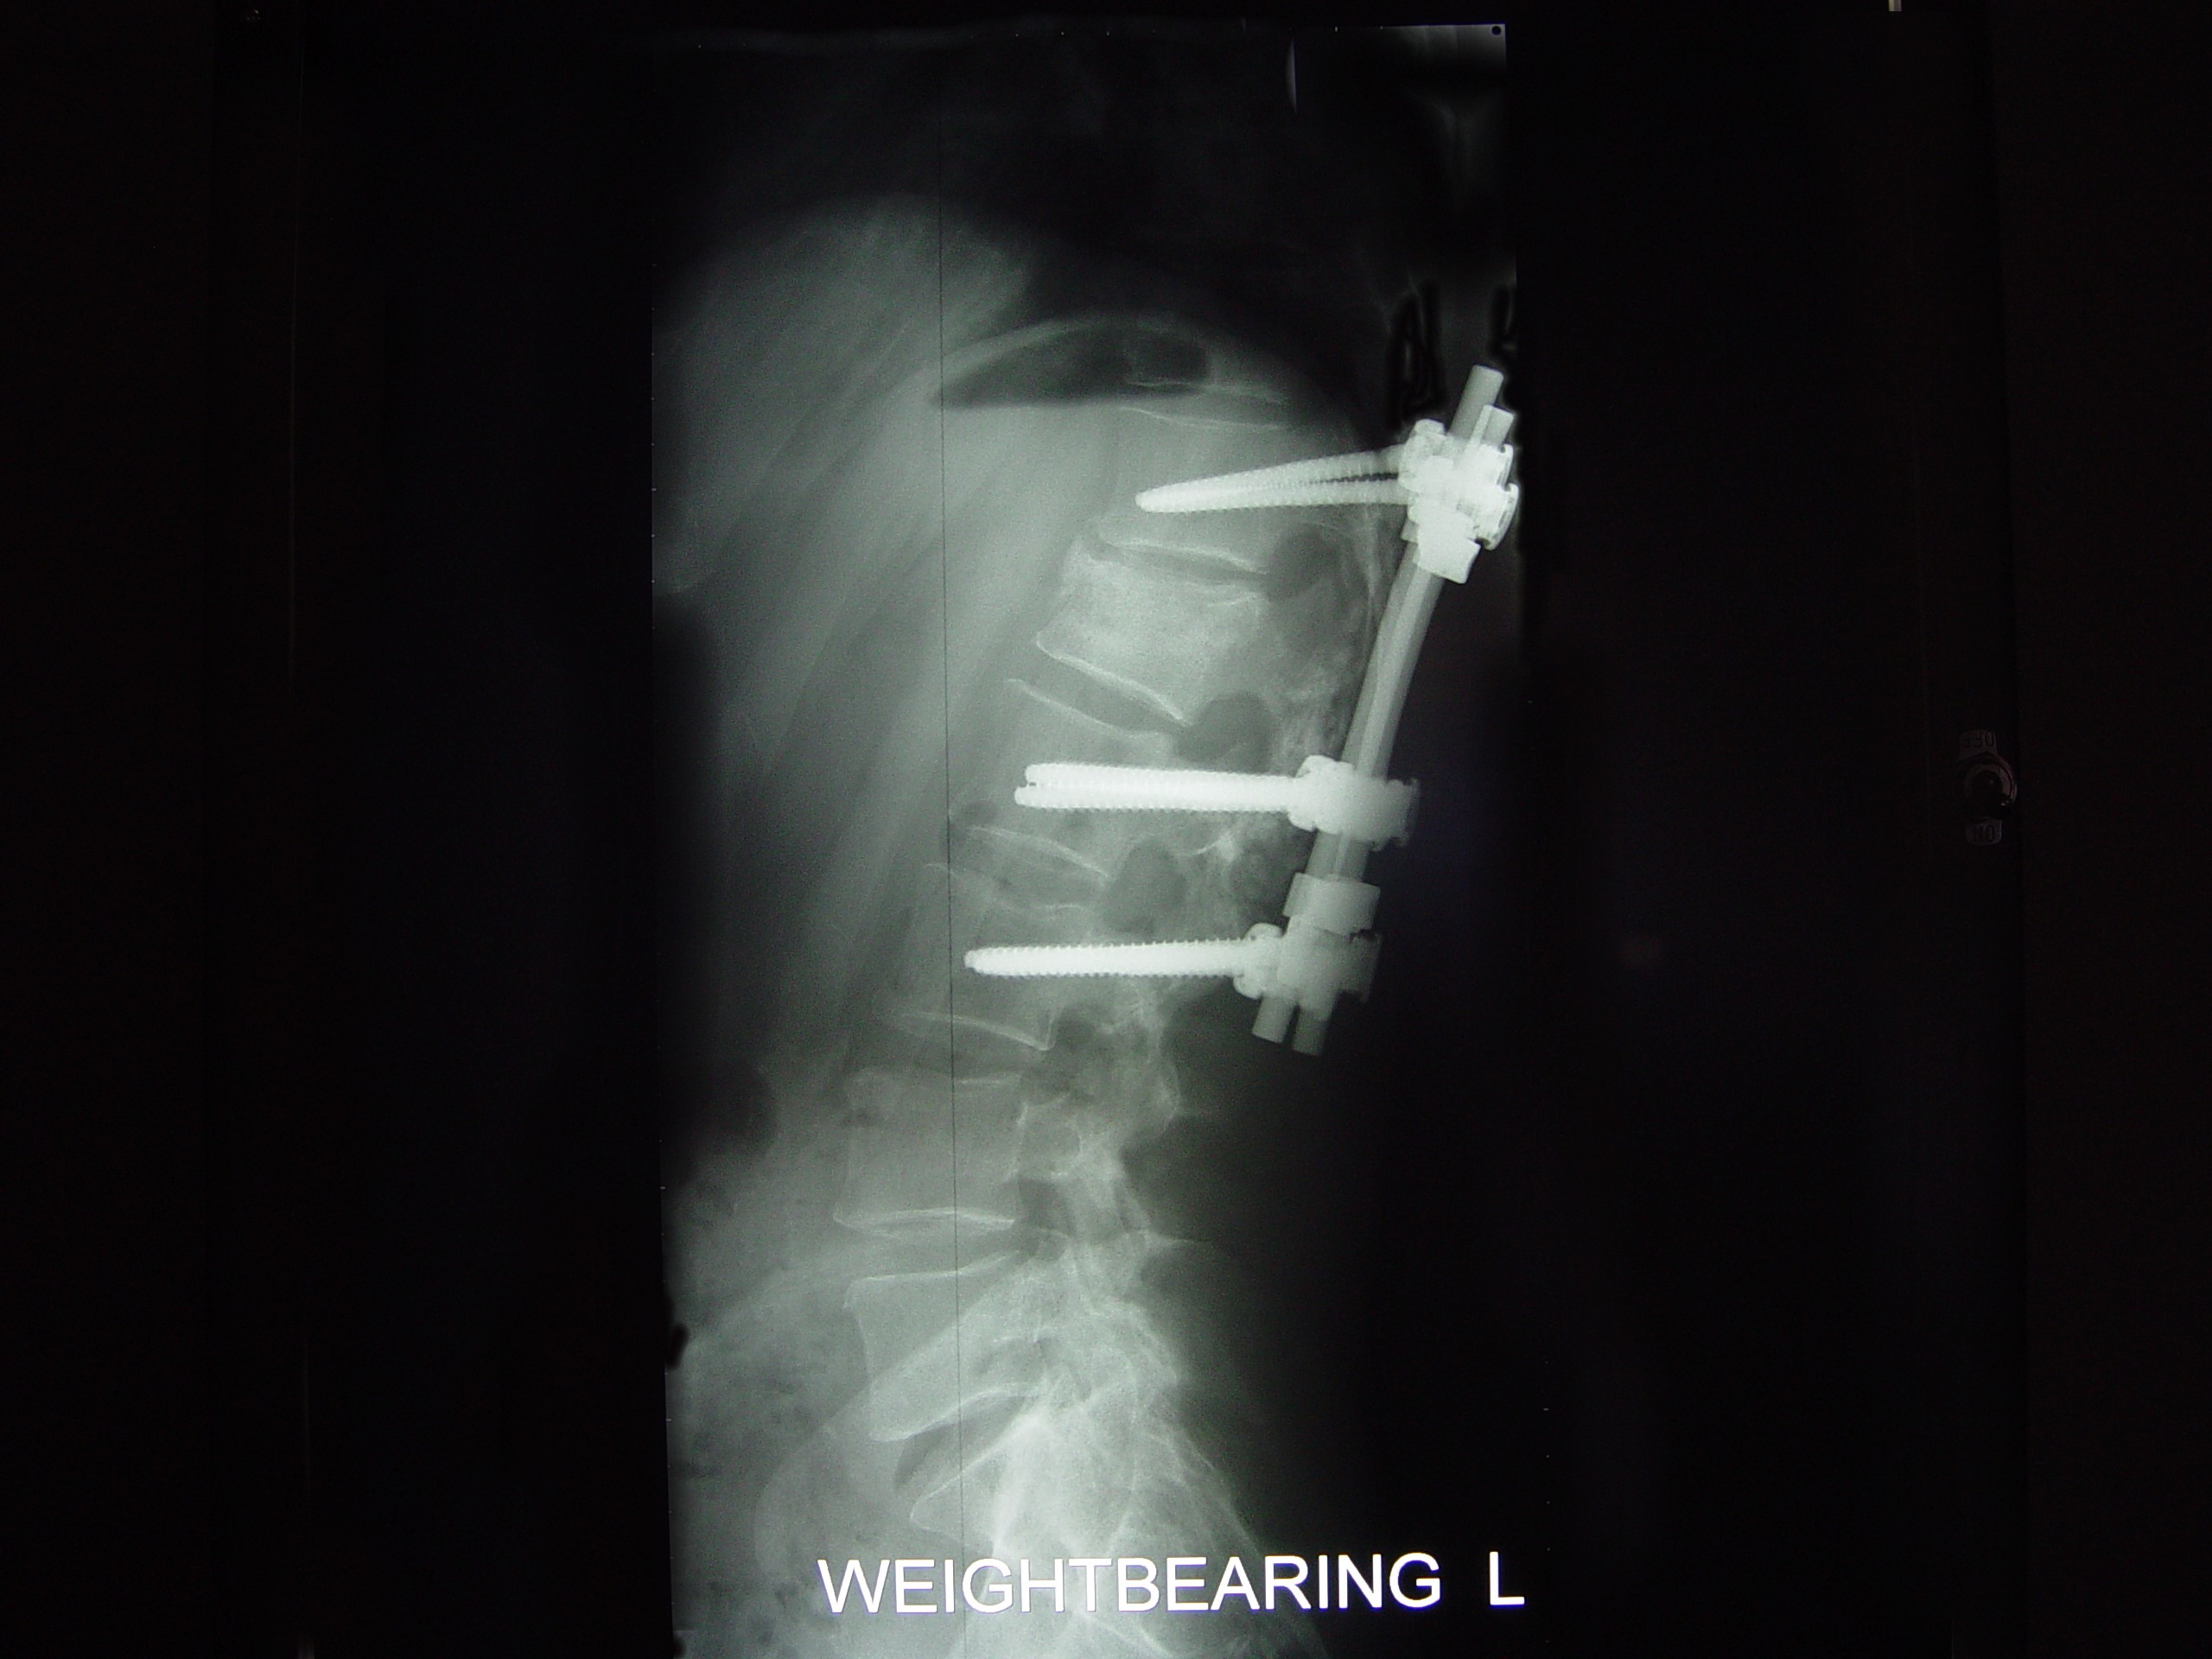

He has TWO rods in his back for support up and down... Two screws at the bottom of each rod and one at the top... He is in recovery at this time more than likely still...

He Faces a LONG three to Four months of bed rest while his back heals up... The Best of luck in all of this. The Doctors were able to do ALL of the surgery through his THIN little body Via his BACK and Did not have to cut his chest etc at all... He has 2 rods in his back and that is NOW confirmed and what I posted last night late is all good...

The hardware is coming out! On April 28th I'm gettin' this monkey off (out of) my back. Hopefully it is the source of the leg pain that has slowed the recovery process.

The Monkey: Side View